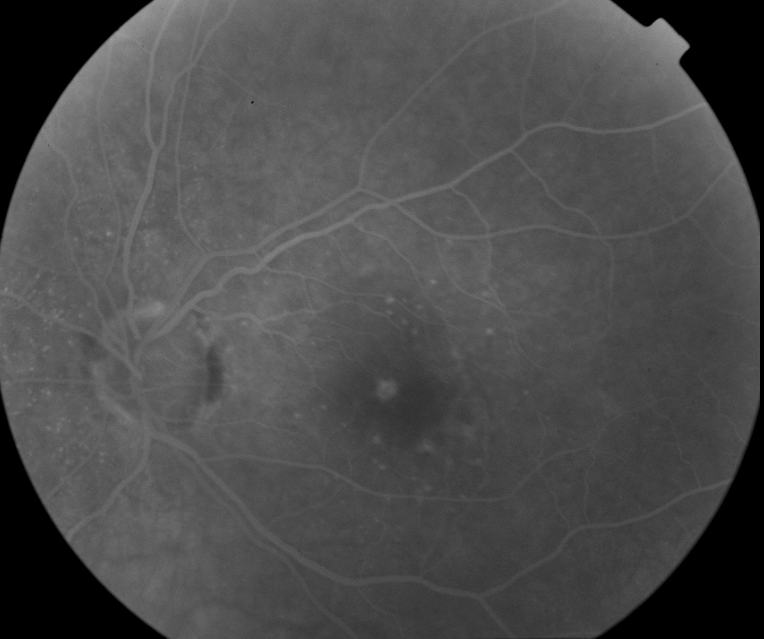

FUNDUS DESCRIPTION: |

OD OS |

OD Red-Free: Pre-Injection: Arterial: A-V: Venous: Recirculation: Late:

OS Red-Free: Venous: Recirc: Late:

Impression